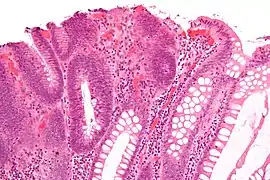

a)Pedunculated adenoma, b) photomicrograph of the same polyp showing an adenoma with low grade dysplasia